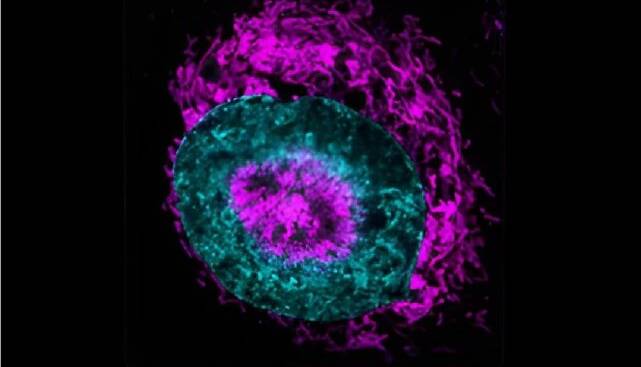

5 نشانه ضعیف شدن ریه ها و بهترین روش تقویت آن چیست؟